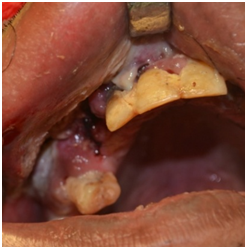

A 48 year old male patient was referred to our outpatient department with history of unsettling facial swelling and uncontrolled diabetes mellitus for which he was hospitalized under the general medicine ward. History revealed that the patient had a fall from the bed in an inebriated state three days prior, following which he developed swelling over the right side of the face and pain in the upper front teeth. In the mean time he was treated by his dentist who extracted the upper right canine and premolar presuming that the swelling in the canine Fossa was caused by dental infection. An intra oral incision and drainage was also performed in order to drain the abscess. On clinical examination he presented with right ‒sided infra orbital swelling with a portion of the overlying skin necrosed. The swelling was seen obliterating the naso labial fold on the same side. Gross edema of the peri‒oral and periorbital tissue with resultant narrowing of the palpebral fissure was noted on the same side (Figure 1). Intraoral examination revealed an extraction socket in relation to upper right canine and premolar and vestibular laceration with slough and poor oral hygiene (Figure 2).

Figure 2 Premolar and vestibular laceration with slough and poor oral hygiene.